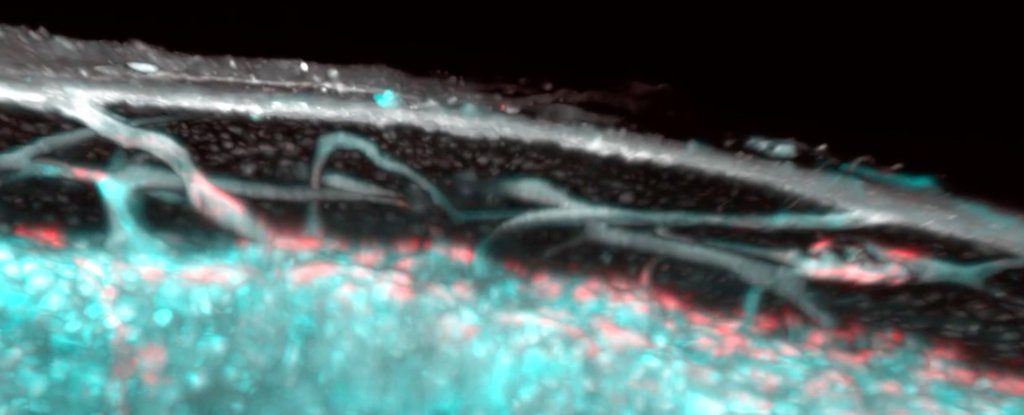

Yeni araştırmaya ilişkin bir yorumda, ‘Kemikte karmaşık bir kan sisteminin varlığına dair kanıtlar oluşmasına rağmen, hücrelerin ve sıvının kemik iliğinden dolaşıma doğru girebilmesinisağlayan moleküler mekanizmalar ve anatomi, belirsiz kalmıştır” diye açıklıyor. Şimdi, bu mekanizmanın temeli ilk defa birkaç yıl önce kaza ile tespit edildi. Bir çalışma için Gunzer, farelerde flüoresanla boyanmış kan hücreleri inceliyordu ve bunların katı kemiğin içinden geçmesi mikroskop altında gözlemledi. Tıbbi literatürde fenomeni açıklayabilecek hiçbir şey bulunmuyor.  Bu alanda neler olduğunun tespit edilebilmesi için yeni bir araştırma projesi geliştirildi. Yeni çalışmada, Gunzer’in ekibi farelerintibialarını (bacak kemikleri) etil sinamat adlı bir kimyasal kullanarak temizledi ve şeffaf hale getirdi.Daha sonra, bir ışık levhası floresan mikroskobu (LSFM) ve X-ışını mikroskobu kombinasyonu kullanılarak, ilk kez bacak kemiklerinin kortikal tabakasından geçen bu küçük TCV’lerin birkaç farklı yüzü tespit edebildiler. Araştırmacılar, bir fare tibyasının 1000’den fazla küçük kılcal damar içerebileceğini ve bunun şaşırtıcı derecede yeterli olduğunu, arteriyellerin yüzde 80’inden fazlasının ve venöz kanın yüzde 59’unun kanallardan geçtiğini söylüyor. Çalışmada yer almayan İsviçre Federal Teknoloji Enstitüsü’nden biyomekanik araştırmacısı RalphMüller, “Bu sistemleri hiç görmedim. Ancak biz de buna bakmadık. Bu benim için bir sürpriz.

Bu alanda neler olduğunun tespit edilebilmesi için yeni bir araştırma projesi geliştirildi. Yeni çalışmada, Gunzer’in ekibi farelerintibialarını (bacak kemikleri) etil sinamat adlı bir kimyasal kullanarak temizledi ve şeffaf hale getirdi.Daha sonra, bir ışık levhası floresan mikroskobu (LSFM) ve X-ışını mikroskobu kombinasyonu kullanılarak, ilk kez bacak kemiklerinin kortikal tabakasından geçen bu küçük TCV’lerin birkaç farklı yüzü tespit edebildiler. Araştırmacılar, bir fare tibyasının 1000’den fazla küçük kılcal damar içerebileceğini ve bunun şaşırtıcı derecede yeterli olduğunu, arteriyellerin yüzde 80’inden fazlasının ve venöz kanın yüzde 59’unun kanallardan geçtiğini söylüyor. Çalışmada yer almayan İsviçre Federal Teknoloji Enstitüsü’nden biyomekanik araştırmacısı RalphMüller, “Bu sistemleri hiç görmedim. Ancak biz de buna bakmadık. Bu benim için bir sürpriz.